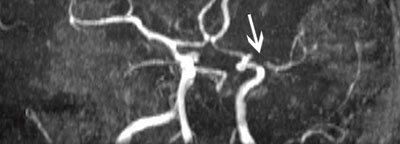

MR viste lette iskemiske forandringer i hvit substans i begge hemisfærer og en 5 mm lang høygradig stenose i proksimale del av venstre a. cerebri media (fig 1).

Sannsynligvis var denne stenosen alene årsaken til pasientens symptomer, men vi kunne med våre undersøkelser ikke utelukke at hennes kontralaterale carotis interna-stenose bidro til hypoperfusjon distalt for stenosen i a. cerebri media.